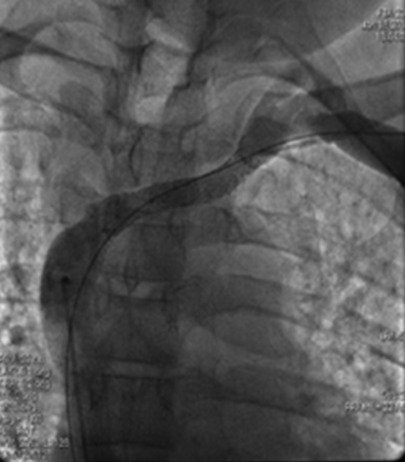

Advanced image-guided procedures performed for complex vascular and organ-based conditions.

Thoracic and abdominal aortic aneurysm – TEVAR & EVAR. Aortic Dissection stenting.

Opening narrowed arteries to restore healthy blood flow.